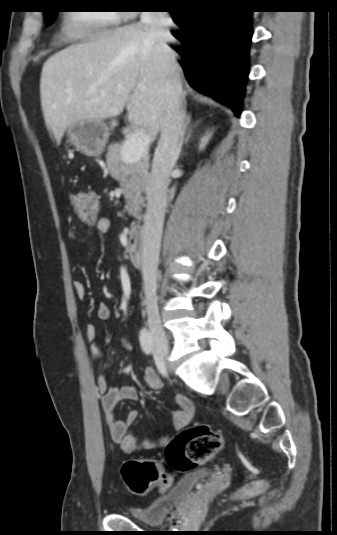

Для диагностики патологии нижней полой вены применяется высокоинформативный быстрый и неинвазивный (то есть не требующий вмешательства в организм пациента) метод исследования – мультиспиральная компьютерная томография (КТ-ангиография). КТ-ангиография позволяет диагностировать патологические изменения нижней полой вены на ранней стадии развития, когда лечение наиболее эффективно.

Метод компьютерной томографии основан на применении рентгеновского излучения. Источник излучения, расположенный в кольцевой части томографа, вращается вокруг зоны исследования и делает послойное сканирование со срезами толщиной от 0,5 мм. Для визуализации кровеносных сосудов обязательно используется контрастное усиление, которое усиливает контрастность сосудов на фоне окружающих тканей и позволяет увидеть патологические изменения на начальной стадии.

Для контрастирования используется йодсодержащий препарат, обладающий высокой рентгеноконтрастностью за счет способности поглощать рентгеновские лучи. Препарат вводится пациенту внутривенно во время исследования и позволяет диагностировать различную патологию нижней полой вены, включая аномалии развития, тромбозы, воспалительные изменения сосудистых стенок, опухолевые образования, прорастающие в нижнюю полую вену или сдавливающие ее извне.